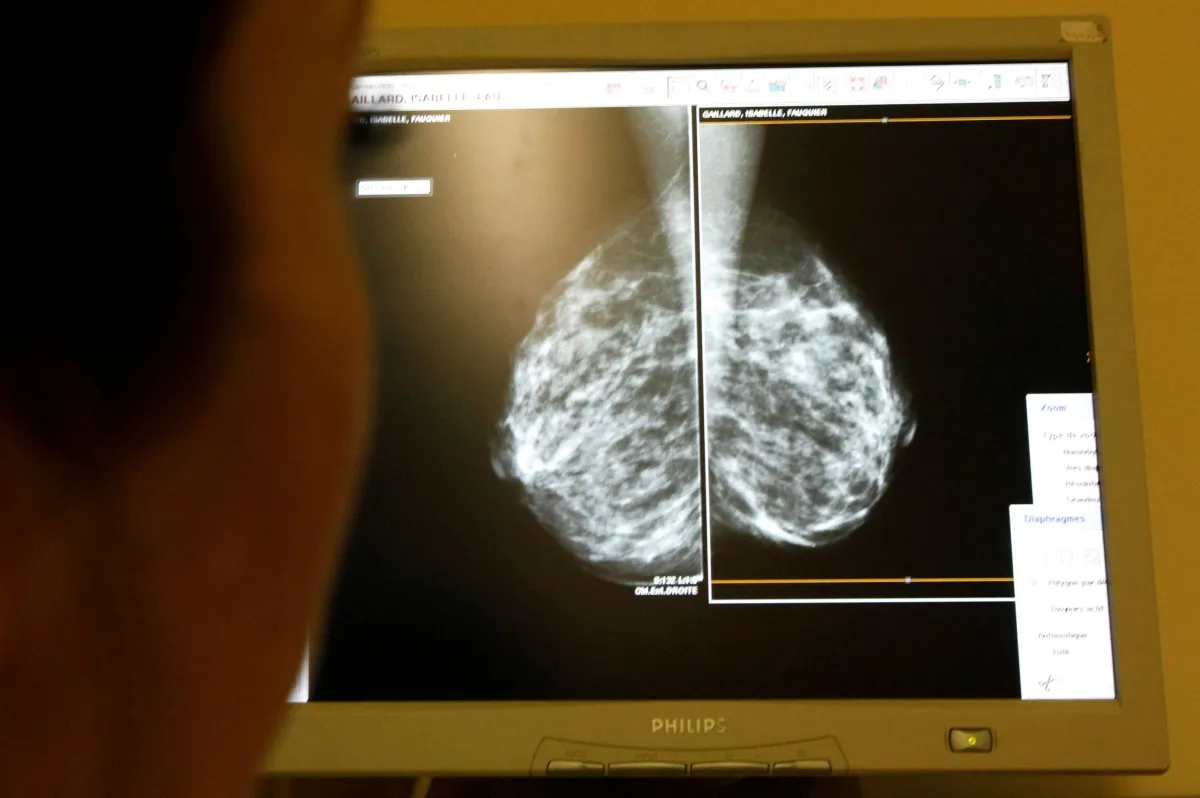

يمكن أن تساعد الفحوصات والفحوصات المنتظمة لأمراض النساء أيضًا في الكشف المبكر.